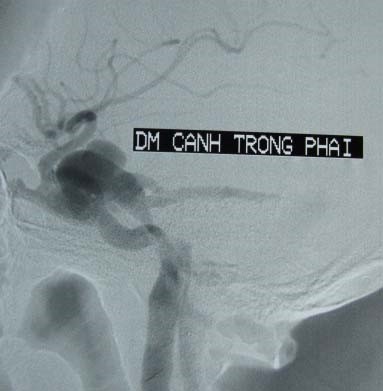

Trung tâm Điện quang từng tiếp nhận người bệnh Nguyễn Văn Đ *. Bệnh nhân sau khi bị tai nạn khoảng vài tháng, xuất hiện lồi mắt, đỏ mắt tăng dần, có thể lác, giảm thị lực, nghe thấy có tiếng thổi hay tiếng ù vùng tai hay vùng mắt tuỳ theo mức độ của luồng thông. Khám thấy lồi và đỏ mắt, nghe có tiếng thổi vùng mắt hoặc thái dương. Trên Siêu âm Doppler thấy tăng tốc độ dòng chảy động mạch cảnh trong bên tổn thương và giảm sức cản, thấy tĩnh mạch mắt giãn, đảo chiều dòng chảy và động mạch hoá.

Phương pháp can thiệp nội mạch là phương pháp sử dụng bóng hoặc vòng xoắn kim loại dưới trợ giúp vi ống thông đưa đến chỗ luồng thông rồi bơm bóng hoặc thả vòng xoắn kim loại làm tắc luồng thông mà vẫn bảo tồn được động mạch cảnh trong. Có thể thả một hoặc nhiều bóng nếu luồng thông lớn. Với các trường hợp lỗ rách phức tạp, nếu không điều trị bảo tồn được động mạch cảnh trong, có thể tiến hành nút tắc mạch mang ở phía trên và dưới luồng thông, hoặc gây tắc qua đường tĩnh mạch. (Hình 1)

Nút thông động mạch cảnh xoang hang: a- Hình lồi đỏ mắt trái sau chấn thương. b- Hình CLVT thấy lồi mắt trái. c- Hình Siêu âm Doppler thấy giãn đảo chiều dòng chảy tĩnh mạch mắt. d- Hình thông trực tiếp động mạch cảnh xoang hang, luồng thông lưu lượng trung bình. e- Sau nút bằng 3 bóng, tắc hoàn toàn luồng thông. f- Hình kiểm tra sau nút luồng thông, mắt trái xẹp hết lồi.